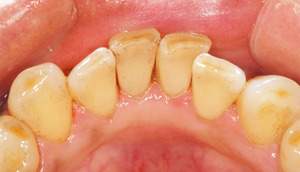

歯石除去

治療前

治療後

| 年齢 | 25歳・男性 |

| 主訴 | 歯石をとりたい・検診 |

| 治療内容 | 各種検査・歯石除去 |

| 治療期間 | 60分 |

| 費用 | 初診料3,000〜4,000円前後 +歯石除去約1,000円 |

| リスク・副作用 | ・処置後に歯がしみることがあります。 ・歯と歯の間に隙間ができるので、息が漏れ発音しにくいと感じることがあります。 ・歯ぐきの炎症が軽減すると歯ぐきが引き締まり、歯が長く見えることがあります。 |

| 担当者所見 | 前歯の裏側にすぐに歯石が溜まってしまいザラザラして気になるとご相談いただいたので適切な歯ブラシの当て方とフロスの通し方をお伝えさせて頂きました。 |